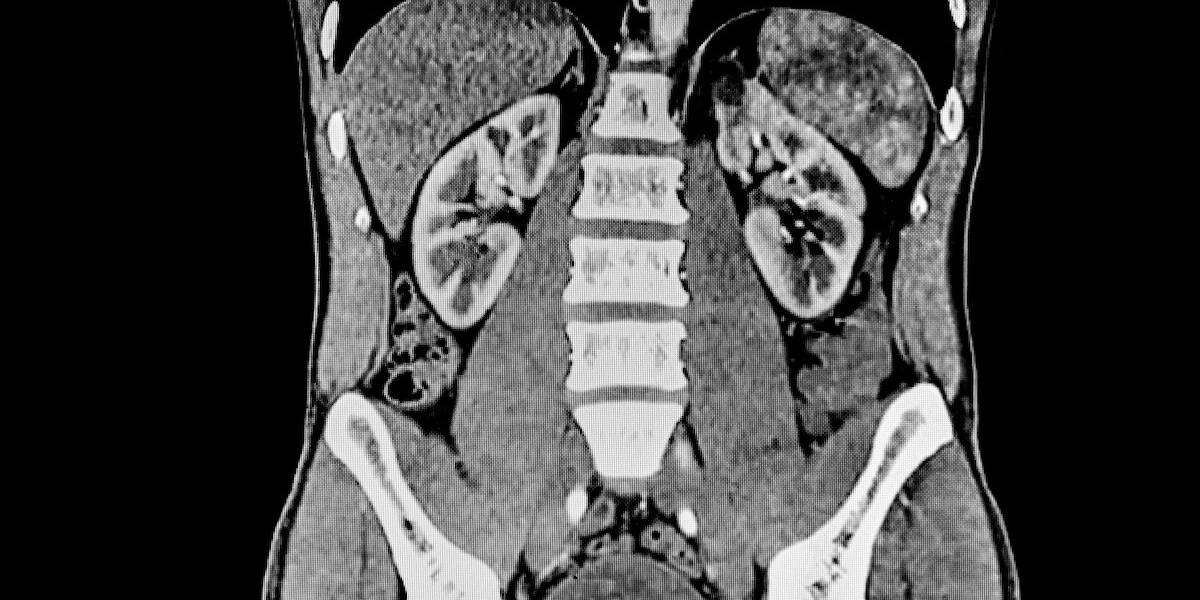

Een onderzoeksteam van de Technische Universiteit München (TUM) heeft een methode ontwikkeld om vroegtijdige nierschade als gevolg van bepaalde kankerbehandelingen te voorspellen. Maanden voordat er een meetbare afname van de nierfunctie gedetecteerd kan worden, beginnen de nieren te krimpen. De onderzoekers zijn erin geslaagd om die trend te detecteren met behulp van een AI-algoritme waarmee CT-scans van de nieren geanalyseerd werden. Daarnaast werden vergelijkbare veranderingen in de milt waargernomen. De nieuwe AI-analyse methode zou er volgens de onderzoekers in de toekomst toe kunnen leiden dat kankerbehandelingen aangepast worden om orgaanschade te voorkomen.

Terwijl factoren zoals de lengte van de nieren of de leeftijd van de patiënt geen betrouwbare voorspellingen opleverden, bleken veranderingen in het niervolume een sterk signaal te zijn: wanneer het niervolume binnen zes maanden na het begin van de behandeling met 10% of meer afnam, was de kans groot dat de nierfunctie binnen nog eens zes maanden aanzienlijk zou afnemen.

“Deze veranderingen in het niervolume zijn heel subtiel. Ze kunnen gemakkelijk over het hoofd worden gezien tijdens routine beeldbeoordelingen omdat artsen zich voornamelijk richten op het opsporen van tumoren en andere belangrijke bevindingen,” legt prof. Matthias Eiber uit, een van de hoofdauteurs van het onderzoek, samen met prof. Rickmer Braren. “Daarentegen kunnen beeldanalyse-algoritmen - mits goed getraind - zelfs deze kleine veranderingen betrouwbaar detecteren,” voegt Dr. Friederike Jungmann toe.